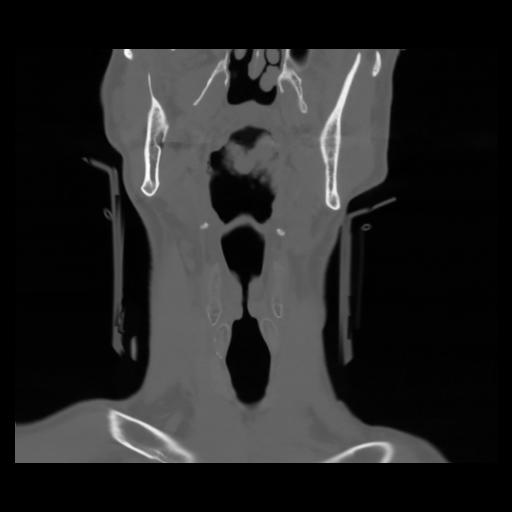

13 P.BLANDAS,,Coronal,2.000,P.BLANDAS,Coronal,